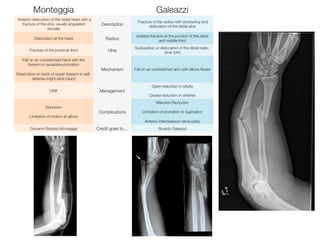

Plain Radiographs

• radial shaft fracture

– commonly at the junction of the middle and distal

third

– dorsal or volar angulation

• dislocation of the distal radioulnar joint

• radial shortening may occur

X- RAY forearm and wrist

A-P view Lateral view